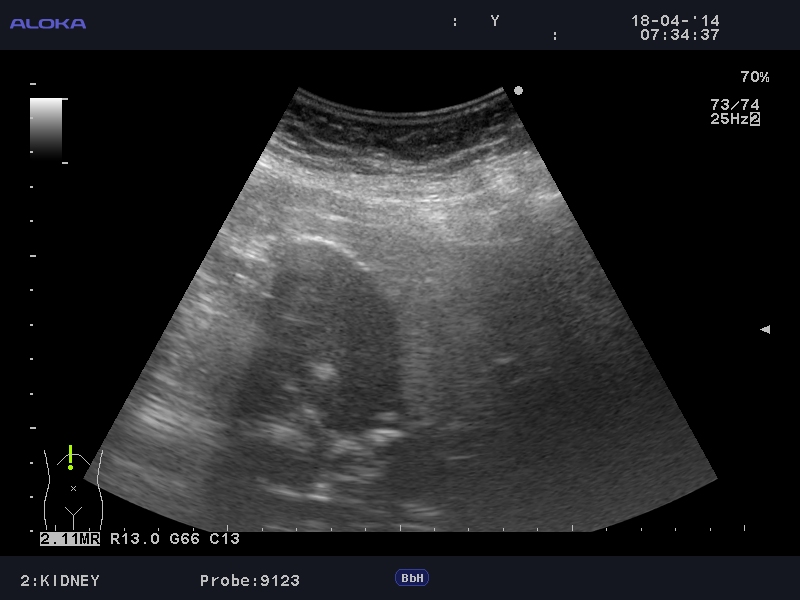

Фарфоровый желчный пузырь (Porcelain gallbladder)

Женщина средних лет без жалоб на здоровье.

Еще случай.

Бабушка из отделения сестринского ухода, без жалоб на боли в животе. Лаб. анализы не изменены.

Если кальциноз стенки полный и содержимое пузыря осмотру не доступно, то есть показания к проведению КТ-МРТ. Если стенки инкрустированы частично (как в представленных случаях) и можно оценить характер содержимого и структуру стенок, то можно ограничиться только УЗИ. Далее, если есть подозрение на опухоль то пациента направляют к онкологу, а он сам определяет дальнейшую тактику.